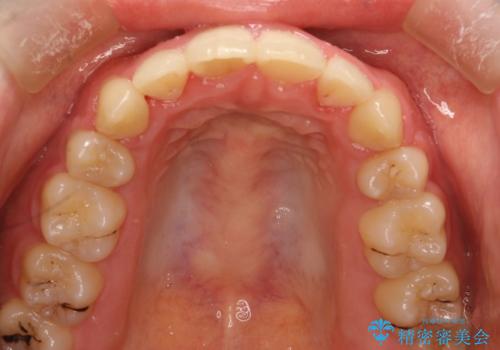

- 上下の全体的ながたつきが気になるとのことで来院されました。

上下左右の前から4番目の歯を抜歯をして、ワイヤー矯正にて並べる計画としました。

全体的ながたつきがなくなり、見た目の印象がよくなりました。